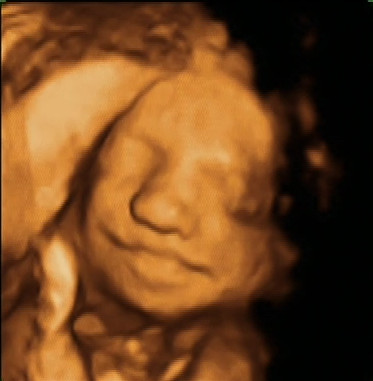

Die dag dat we onze zoon voor het eerst ‘zagen’

Gisteren zou de meest depri dag geweest zijn van het jaar. Niet voor ons, want wij gingen naar de gynea voor een zogenaamde 3D echo van onze zoon.

Eerst kwam hij goed in beeld